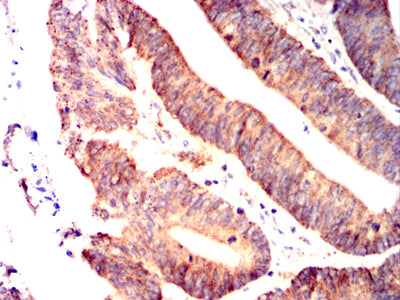

- Immunohistochemical analysis of paraffin-embedded human colon cancer tissues using IRF3 mouse mAb with DAB staining.